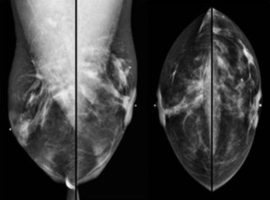

Adenoid Cystic Carcinoma of the Breast: A Multi-institutional Case Series and Review of Literature

Dileo R*, Keshava VE, Kumar SA, et al. (USA)